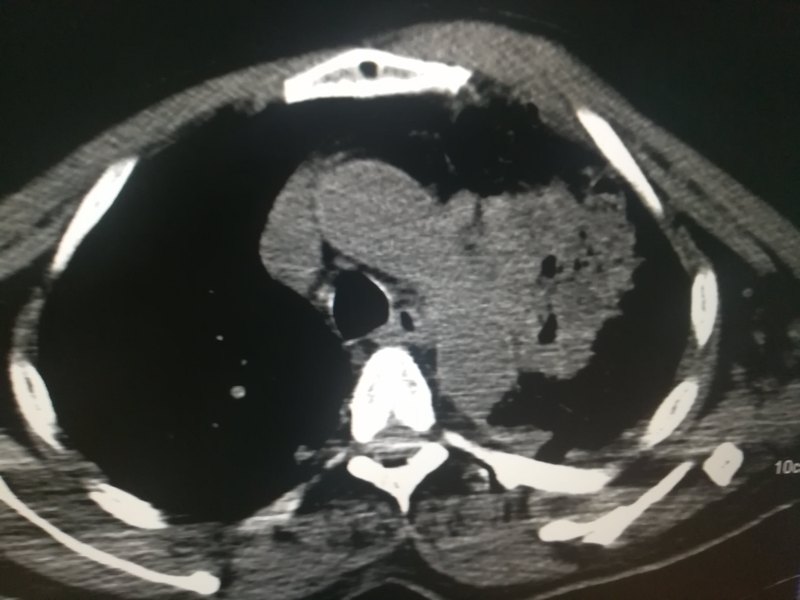

老年男性,刺激性咳嗽癥狀嚴(yán)重,可待因都止不住咳嗽。入院查體發(fā)現(xiàn)左側(cè)中心型肺癌,左上葉支氣管狹窄閉塞。 病理結(jié)果為腺癌。如圖1.2所示,為治療前病人的胸部CT圖片。 介入治療兩次后,病人咳嗽癥狀緩解,停服可待因,咳嗽亦無(wú)反復(fù)。 復(fù)查CT,患者原來狹窄閉塞的支氣管已經(jīng)復(fù)通。 腫瘤明顯縮小,縮小到幾乎看不到了才是這個(gè)病人好轉(zhuǎn)的原因。 介入治療后肺門腫塊消失,氣管復(fù)通。 介入治療兩次后,病人咳嗽癥狀緩解,停服可待因,咳嗽亦無(wú)反復(fù)。 復(fù)查CT,患者原來狹窄閉塞的支氣管已經(jīng)復(fù)通。 腫瘤明顯縮小,縮小到幾乎看不到了才是這個(gè)病人好轉(zhuǎn)的原因。 晚期肺癌,做介入治療。